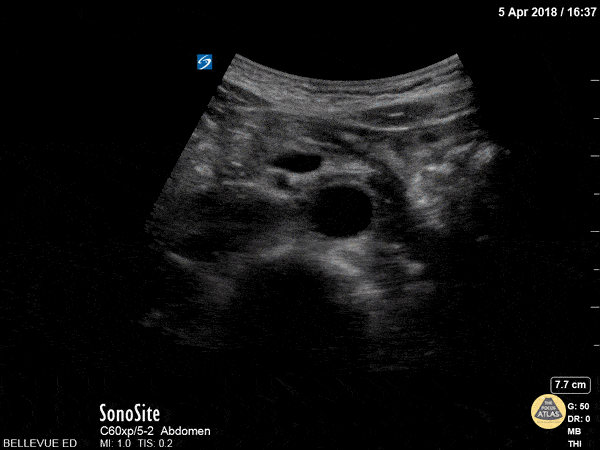

In the center of the screen we see the distal aorta in transverse view. As the probe is moved caudally, the aorta bifurcates into the two common iliac arteries. Deep to the aorta we see the round hyperechoic edge of the vertebral body and to the left of the aorta we see the more compressible inferior vena cava.